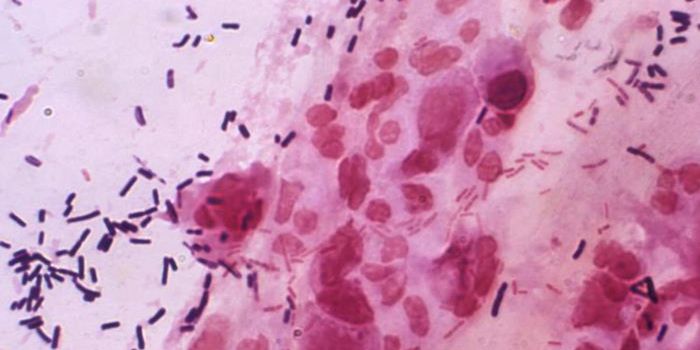

FEB 27, 2015Health & MedicineClostridium difficile (C. difficile, or C. diff) caused almost half a million infections among patients in the United St ...

FEB 27, 2015Health & MedicineATLANTA -- A nasty intestinal bug sickens nearly twice as many Americans each year as was previously thought, according ...

SEP 25, 2015MicrobiologyClostridium difficile is a Gram positive, rod-shaped bacterium commonly found in the soil. However, a small number ...